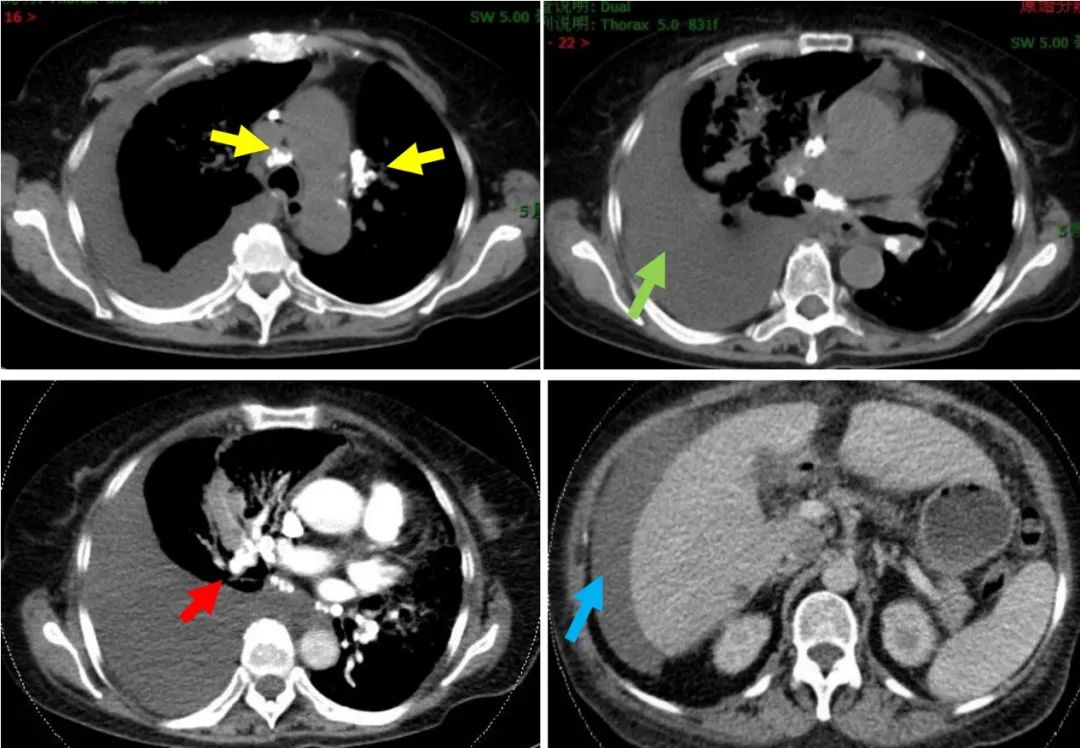

胸部增强CT(2017-02-14):双肺内多发斑片影、蜂窝状影及结节影,伴双肺气管、支气管壁稍增厚,考虑炎症,建议治疗后复查。右侧胸膜腔大量积液。右肺中下叶压迫性肺不张。纵隔及双肺门多发淋巴结钙化。胸主动脉及双侧冠脉钙化。腹水。CTPA:右肺下叶肺动脉未见明显显影,左肺下叶肺动脉显影较差。余肺动脉未见明显充盈缺损。

图1:胸部CT(2017-02-14)提示双肺斑片影、蜂窝状影及结节影,伴双肺气管、支气管壁稍增厚、右侧大量胸腔积液。

图2:胸部CT(2017-02-14)纵隔窗:黄色箭头示:纵隔及双肺门多发淋巴结钙化;橙色箭头示:右侧大量胸腔积液,红色剪头示:CTPA右肺下叶肺动脉未见明显显影,蓝色剪头示:肝周见腹水。